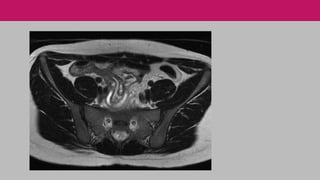

RESSONÂNCIA MAGNÉTICA

Sem radiação.

Exame demorado.

Pouco disponível e de alto custo.

Na gravidez: exame seguro para a gestante, mas o

contraste com gadolínio ultrapassa a membrana

placentária e deve ser evitado no primeiro

trimestre especialmente.

RESSONÂNCIA MAGNÉTICA Sem radiação. Examedemorado. Pouco disponível e de alto custo. Na gravidez: exame seguro para a gestante, mas o contraste com gadolínio ultrapassa a membrana placentária e deve ser evitado no primeiro trimestre especialmente.